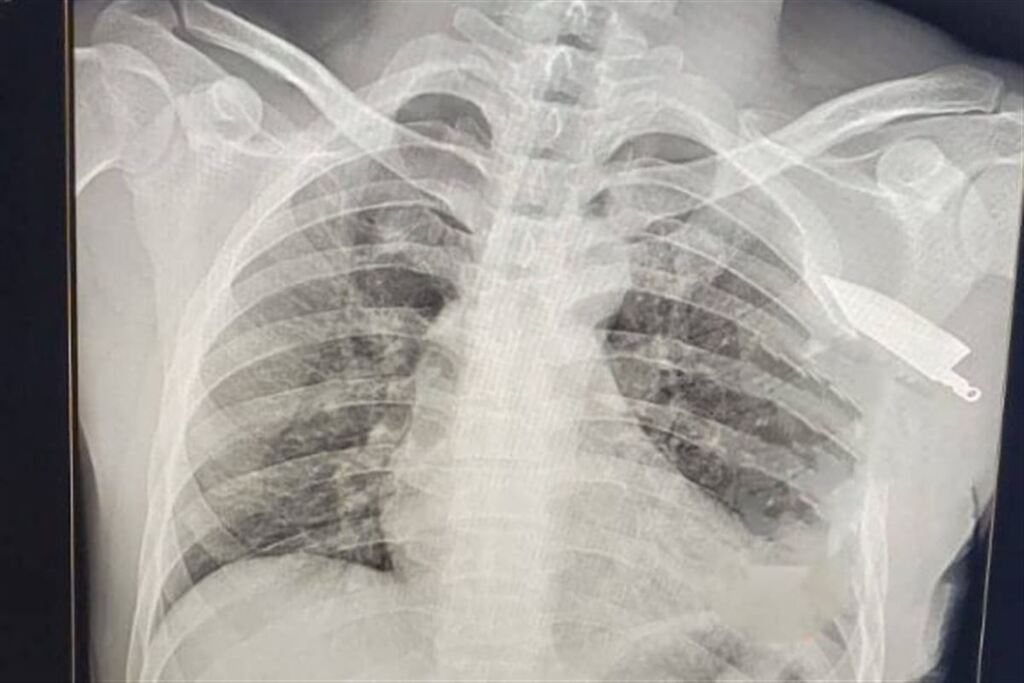

Homem fica com faca presa na clavícula após tentativa de assassinato em Rosário do Sul